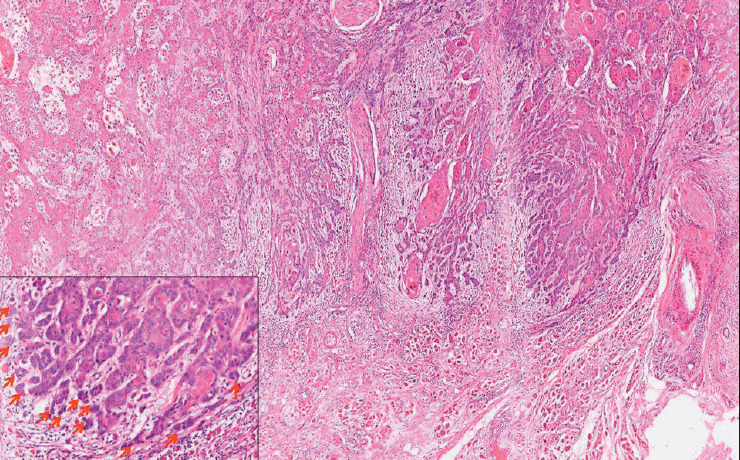

目的:口腔鳞状细胞癌是世界上最常见的头颈部恶性肿瘤。肿瘤出芽是一种组织病理学特征,其特征是在侵袭性肿瘤前部的基质中分散存在孤立的单个/小簇癌细胞。在印度,其在唇部和口腔鳞状细胞癌中的预后意义尚未得到太多研究。本研究的目的是在印度北喀拉拉邦的一个三级癌症中心对333例口腔鳞状细胞癌患者进行大型单中心回顾性队列研究,探讨肿瘤出芽在预后中的作用。材料与方法:从病理档案中检索2018 - 2020年333例口腔鳞状细胞癌的初切切片,由2名独立病理学家对肿瘤出芽及其他组织病理参数进行评估。生存数据从患者档案中收集。结果:我们使用卡方分析发现肿瘤出芽与其他已知的组织病理学预后因子之间存在显著关联。单因素logistic分析显示,肿瘤出芽、浸润深度(bbb10 mm)、最坏浸润方式5和神经周围浸润与局部复发/远处转移显著相关。多因素logistic回归分析发现肿瘤出芽是局部复发/远处转移的独立预后指标。单因素cox比例分析显示,口腔鳞状细胞癌患者的肿瘤出芽、浸润深度(bbb10 mm)、最坏浸润方式5、病理T4分期和神经周围浸润与总生存期降低和无病生存期差相关。多变量cox比例分析显示,肿瘤出芽是总生存期下降和无病生存期差的唯一独立预测因子。结论:基于本研究,我们可以得出结论,肿瘤出芽是一个简单可靠的独立预后指标,有助于口腔鳞状细胞癌患者的个性化治疗。

Objective: Oral squamous cell carcinoma is the most common head and neck malignancy reported worldwide. Tumor budding represents a histopathological feature characterized by the presence of isolated single/small clusters of cancer cells dispersed within the stroma at the invasive tumor front. Its prognostic significance has not been studied much in lip and oral squamous cell carcinomas in India. The aim of this study was to investigate the prognostic role of tumor budding in a large single-center retrospective cohort of 333 patients with oral squamous cell carcinoma at a tertiary cancer center in North Kerala, India.